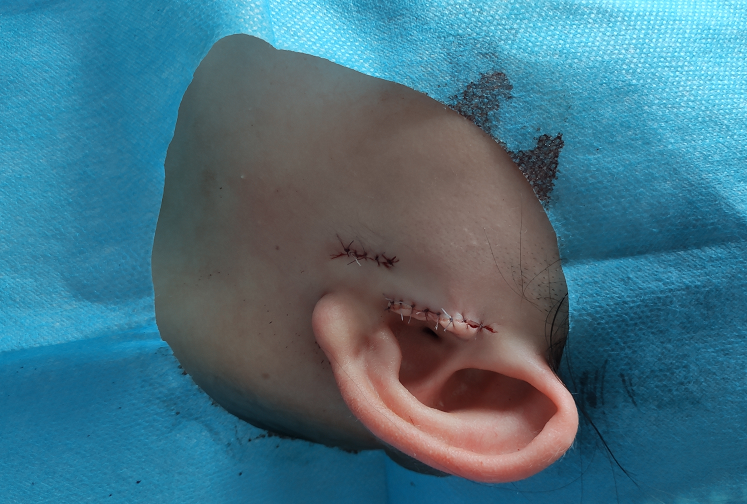

耳朵长了“小赘肉”咋办?丨我院成功为一名“先天性附耳”小患儿进行了手术切除~

你有见过耳朵长 小赘肉的吗? 在医学上被叫做附耳! 附耳,又称副耳或耳赘 是一种常见的先天性耳畸形 附耳虽不会影响健康 但影响人的整体形象 尤其,是在孩子成长阶段 外形上的